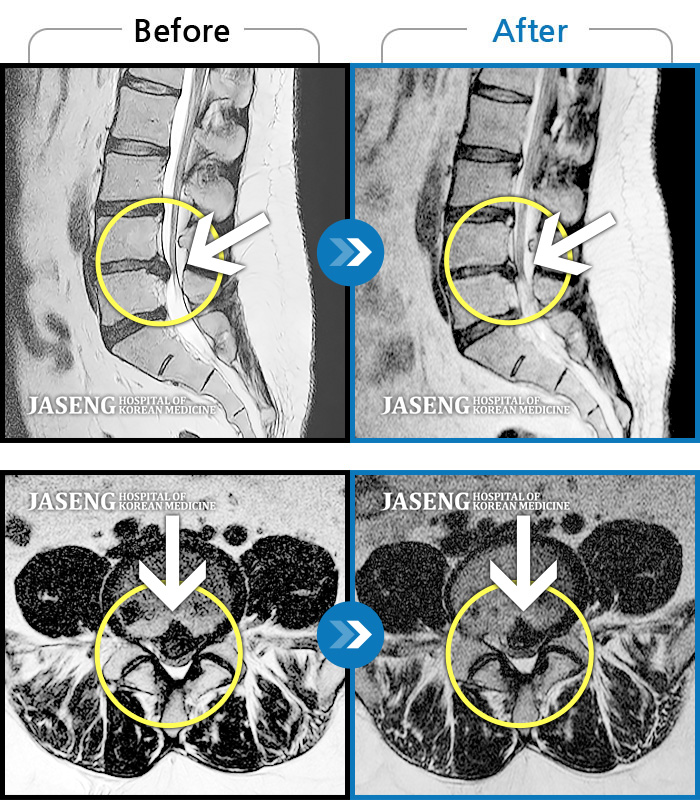

허리디스크

인천 · 조남훈 원장

좌측 허리, 골반, 다리 바깥쪽으로 통증과 저림

촬영시기

2019.07.12 ~ 2020.02.18

2020.02.21